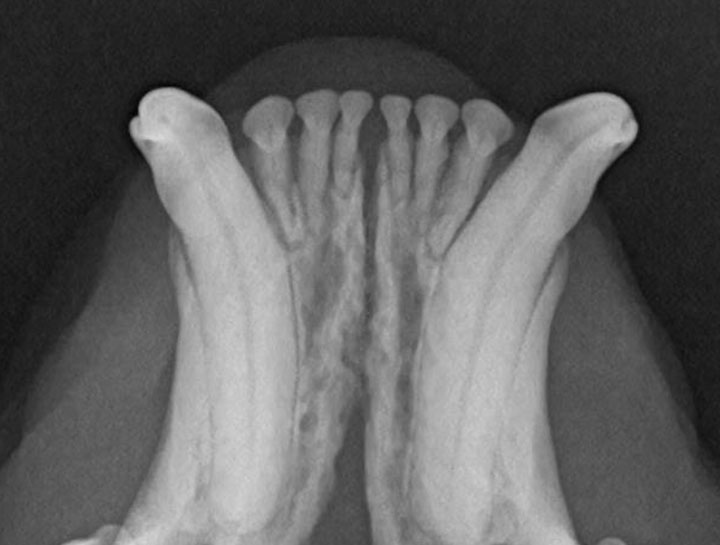

Digital Dental Radiology

Non-invasive techniques for dental health